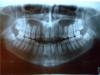

Удача Опубликовано 27 октября, 2009 Поделиться Опубликовано 27 октября, 2009 Здравствуйте, уважаемые доктора!Дочери 18 лет, в детстве носила пластинки, на ВЧ удалены 2 зуба. Сейчас, то ли ВЧ уехала назад, то ли нижняя выдвинулась вперед, скученность зубов на НЧ.Интересует Ваше мнение: можно ли данную ситуацию исправить брекетами, или потребуется операция.Какие зубы необходимо удалить? Ссылка на комментарий

Премоляр Опубликовано 27 октября, 2009 Поделиться Опубликовано 27 октября, 2009 Возможно,сегодняшние проблемы с прикусом вызваны удалением двух зубов на в.ч.(пластинку наверняка мало носила...а потом вообще перестала). Верхняя челюсть сузилась...ниж.чел. занимает вынужденное положение,профиль уплостился...Все это поддается лечению...Возможно с удалением на н.чел. для нормализации перекрытия и контактов+расширение в.ч. Необходима конс.ортодонта со всеми необходимыми расчетами и адекватным планом леченияП.С. Не было ли родственников с мезиал.прикусом(ниж.чел. вперед выступает)??? Ссылка на комментарий

Удача Опубликовано 27 октября, 2009 Автор Поделиться Опубликовано 27 октября, 2009 Да, к сожалению, прикус и зубки кривые достались по наследству. Верхняя челюсть всегда была очень узкой, зубам некуда было расти, поэтому пришлось удалять. А пластинку носила лет 6, лечение прекратили, когда врач посчитала, что все исправлено. Прикус был правильный. Ситуация ухудшилась за последние 2-4 года, может 8 давят? 8-ки внизу однозначно надо удалять? И если наверху удалены 2 зуба, то означает ли это, что внизу тоже придется? Ссылка на комментарий

Force Опубликовано 28 октября, 2009 Поделиться Опубликовано 28 октября, 2009 Брекеты однозначно. Хирургия (ортогнатическая) вряд ли необходима. Удаление восьмерок однозначное. Удаление премоляров на нижней челюсти под большим вопросом, но возможно - необходимо расчитывать трг, анализировать ситуацию, проводить гнатологическое обследование. Что собственно называется "планированием" и исправлять. Ссылка на комментарий